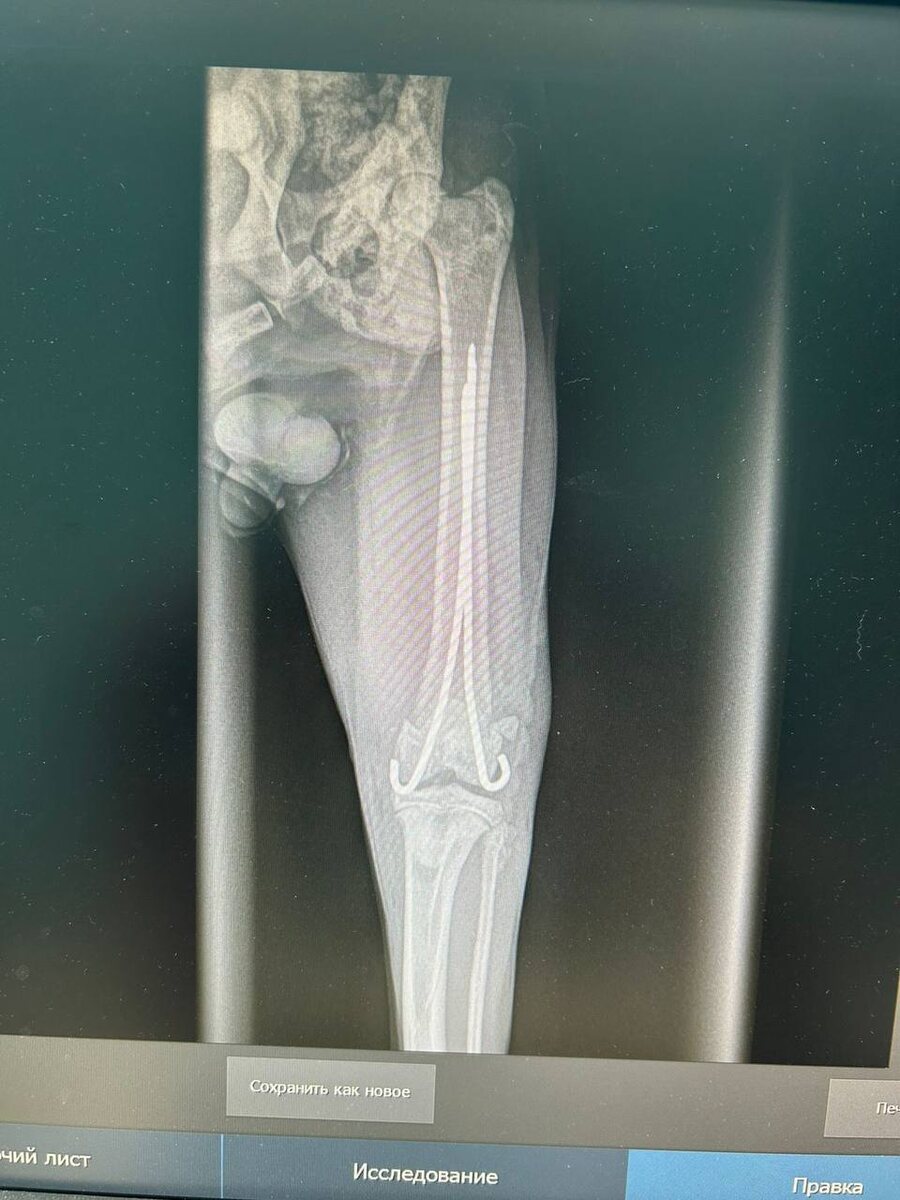

Кузе только что закончили делать операцию !

Ник поставили спицы в бедро(фото прилагаю) сразу кастрировали!